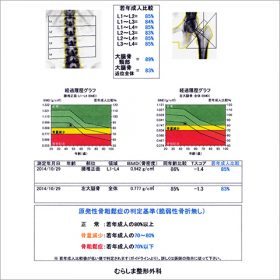

骨密度検査

混雑具合にもよりますが、受診当日に受けて頂く事も可能です。

10分程で検査は終了し、当日に検査結果を説明しつつ患者様に合わせた治療や生活指導を行います。

- 骨折や骨折の連鎖を起こさないための骨粗鬆治療では、継続が重要となりますが、中々実感が得られないため途中で断念してしまう患者様も多いです。

- 当院では担当スタッフの研修会への参加や定期的な勉強会を通じ、患者様の治療継続のためのスタッフの知識・意識の向上にも努めています。